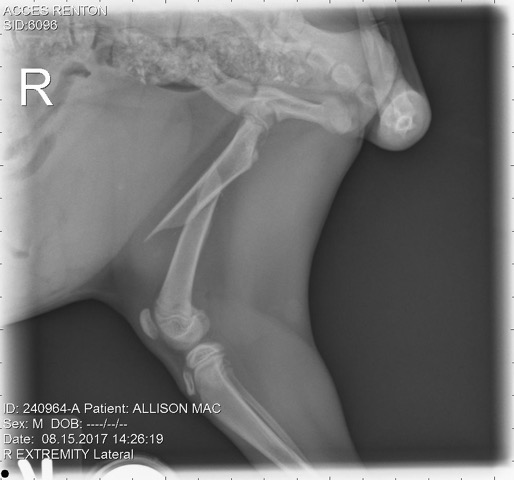

I cannot express the thanks and gratitude I have for Frankie's Friends, Virginia Piper, and the people at BluePearl. I am a single father trying to give my kids the great life experience of having pets, as my parents did for me. Asking for help was very new for me, but our kitten's injury was sudden, severe, and at a tough financial time.